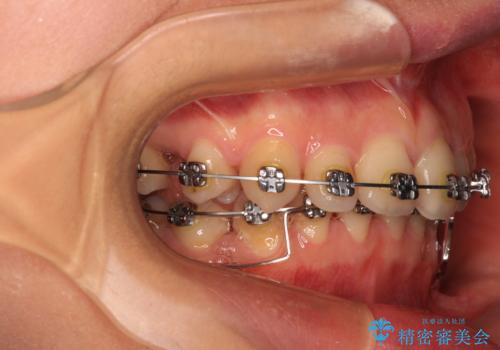

上下臼歯の咬み合わせ改善には補助装置を、深い咬み合わせ改善にはユーティリティーアーチを活用し、ワイヤー装置にて矯正治療を行うこととしました。

甚大な咬合力に抵抗して過蓋咬合を改善する必要があり、更には口元が引っ込みすぎることがないように仕上げていく必要もあったため、治療期間は3年を超えましたが、当初計画通りの仕上がりで治療を終えることができました。